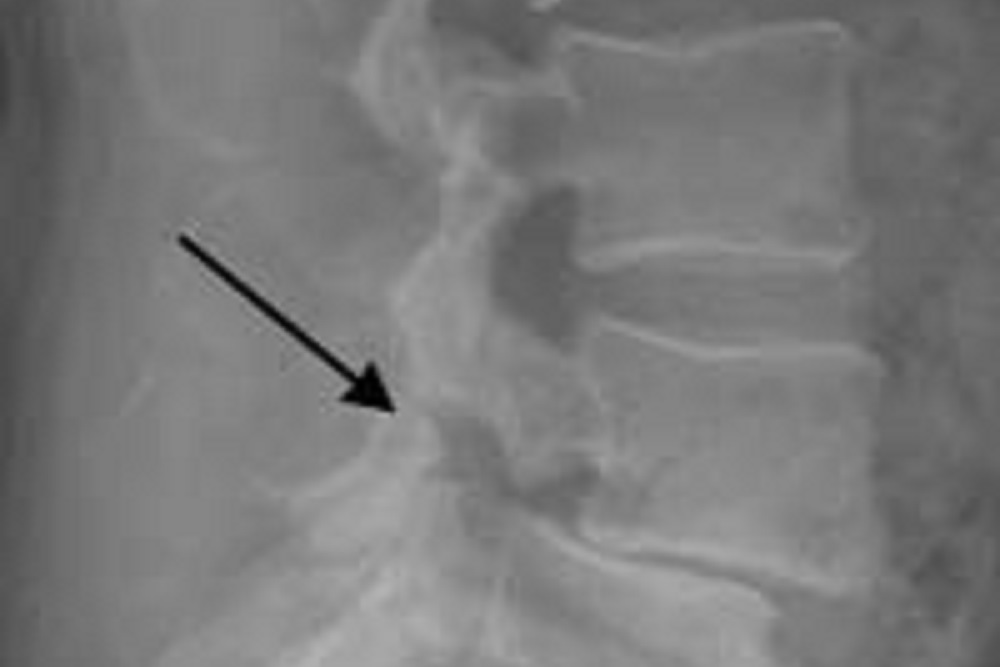

Patients given Evenity for 12 months followed by alendronate saw reductions in vertebral fracture incidents. | File photo

Patients in the study given Evenity for 12 months followed by alendronate saw reductions in vertebral fracture incidents through 24 months as well as reductions in clinical fractures and non-vertebral fractures when compared to patients treated solely with alendronate.